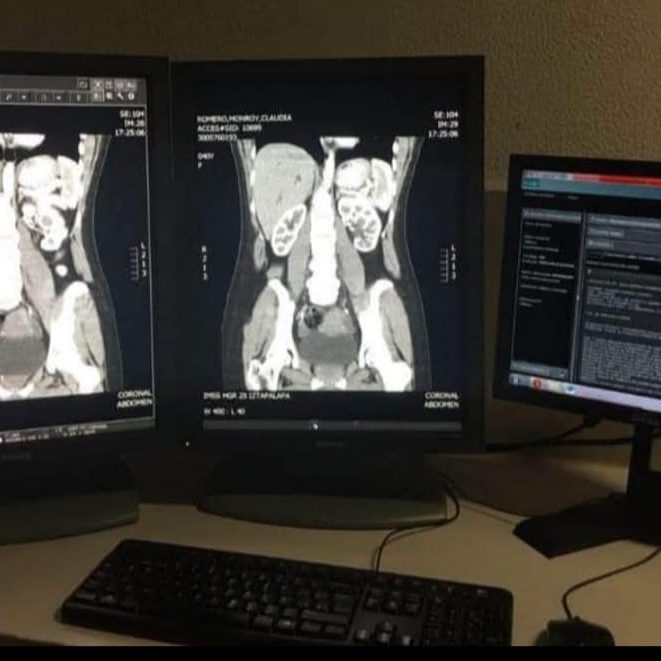

Cursos para comprender la correcta interpretación de placas ultrasonidos y radiografías, por medio de placas reales de mastografia, ultrasonidos, radiografias, etc.

Tomografía Axial Computada

Oportunidades de formación adaptadas a las necesidades de cada alumno.